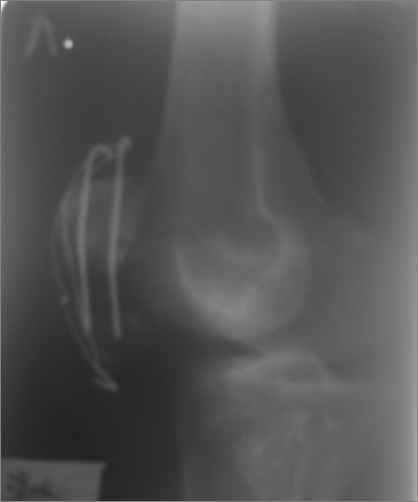

а рентгенкартинки на  пленке от 06.07.2009года  выполнены,  после разваливания  металлоконструкции.

Имя     : 06.07.2009 г.jpg

Тип     : image/jpeg

Размер  : 4443 байтов

Описание: отсутствует

Url     : http://weborto.net:8080/pipermail/ortho/attachments/20090710/17fd1643/attachment-0004.jpg